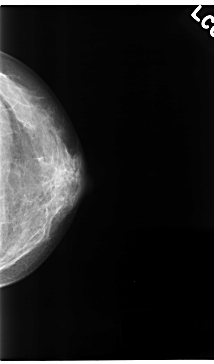

C_0134_1.RIGHT_CC

RIGHT_CC LINES 4744 PIXELS_PER_LINE 2696 BITS_PER_PIXEL 12 RESOLUTION 50 NON_OVERLAY